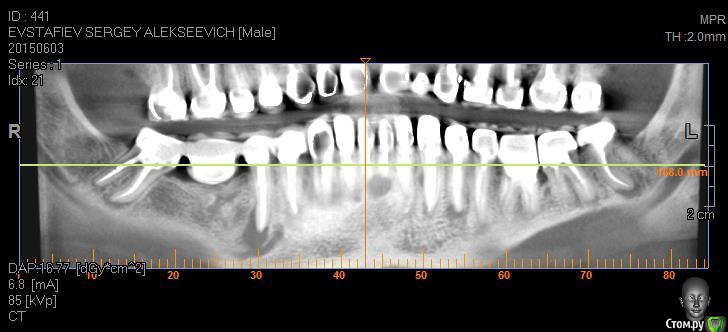

Evstafjev Опубликовано 25 октября, 2015 Поделиться Опубликовано 25 октября, 2015 (изменено) Здравствуйте уважаемые форумчане! Возможно пишу не в ту ветку форума, но мне кажется что эта самая близкая.Приключилось со мной настоящая беда. Расскажу по порядку.Лет 5 назад в виду совсем плохой ситуации с зубами мне предложили и воплотили следующую методику лечения: депульпировали все зубы и покрыли металлокерамическими коронками. Каналы пломбировали гутаперчей, и укрепили титановыми штифтами. Я был безмерно счастлив. Во первых что через все это "прошел" во вторых что стал нормальным человеком с красивой улыбкой и с возможностью "жевать полным ртом".Но с одним зубом у меня всетаки возникла проблема. Года через 2 после лечения заболел сильно верхний 5-й зуб. Я пошел к врачу, ничего особого не заметили и сказали пропить курс антибиотиков а потом придти снова. Я пропил, зуб прошел, плюс обстоятельства сложились, и я не пришел к врачу. Все было хорошо. Но через какое то время (довольно продолжительное) я заметил небольшую шишечку у проблемного зуба на десне. Это оказался свищ. Абсолютно не беспокоил, поэтому я его не сразу и заметил. Этим летом, в виду переезда на постоянное место жительство в другой город, я решил что нужно перед отъездом решить вопрос с зубом. Пошел к врачу, там посовещались и решили что дабы не разбирать конструкцию попробуют сделать резекцию верхушки корня. Отправили на КТ. Сделал КТ 5х5 и увидел что у соседних зубов на корнях также "шишки". Испугавшись сделал КТ всей полости, и о ужас..... на каждом зубе есть такие же "шишки"!!! Прилагаю снимки сделанные из программы КТ, так как все содержимое диска с КТ сюда не поместить, если только через файлообменник, но объем большой и врятли кто то захочет скачивать.Врачи толком ничего не говорят. Сами озадачены. Сказали что раз картина тотальна то то что они плохо пролечили исключено, а что это реакция организма. Решили пока в качестве эксперимента пролечить через канал проблемный 5-й зуб. Протезист сказал что штифты выкручиваются без проблем. Распилил коронку вывернул штифт и далее терапевт начал лечение используя физиопроцедуры с током. Лечили 2-3 месяца. Запломбировали гутаперчей и закрыли временной пломбой. Сказали нужно хорошенько подождать чтобы понять помогло ли лечение. Вот на днях будут смотреть что вышло.Подскажите уважаемые специалисты, каково Ваше мнение по ситуации. Так прискорбно понимать что я в 36 лет похоже лишился всех зубов...PS:Пока лечили зуб параллельно у меня заболели зубы на нижней челюсти. Делали разрез, пил антибиотики - кошмар. Изменено 25 октября, 2015 пользователем Evstafjev Ссылка на комментарий

Evstafjev Опубликовано 26 октября, 2015 Автор Поделиться Опубликовано 26 октября, 2015 Я вот думаю что фото из КТ не полностью показывают картину, не очень я владею данным программным обеспечением, с трудом поймал ракурс. Но не очень информативно. Если крутить мышкой отдельно у каждого зуба тот там картинка "пострашнее" Ссылка на комментарий